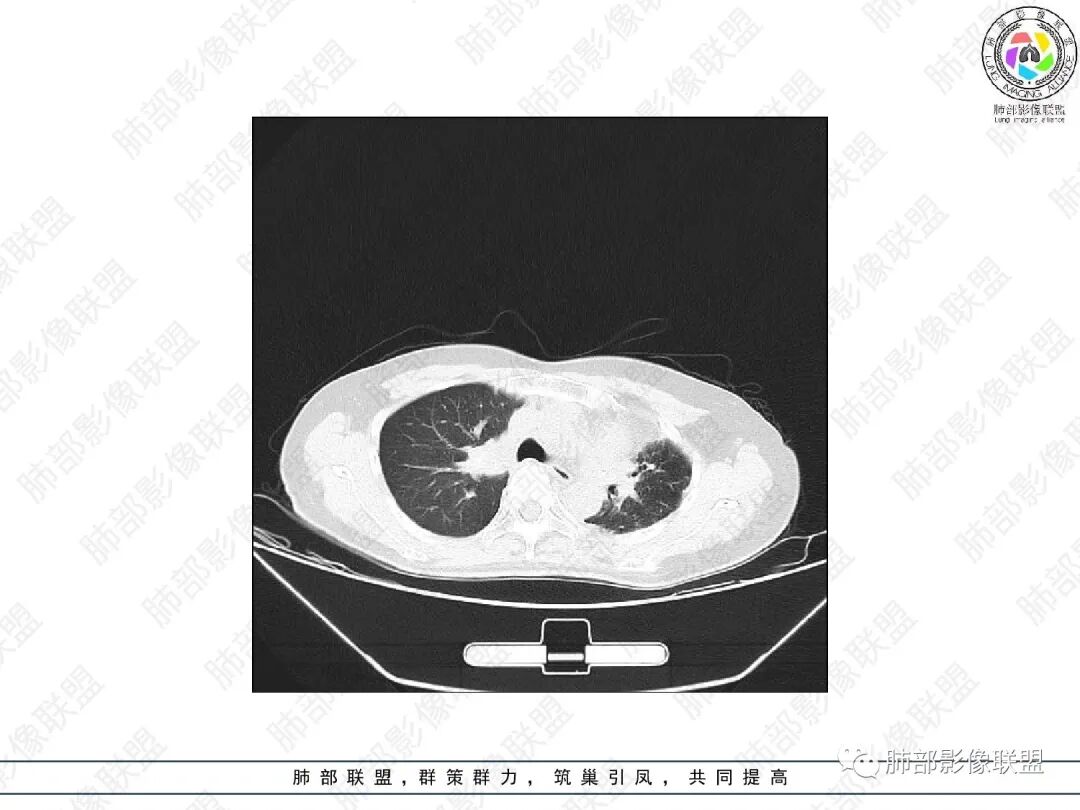

2.胸部CT:右肺上叶及中叶不规则块状影,沿支气管走行方向指套样影,支气阻塞湖嵌塞,腔内可见高密度影。灶周可见磨玻璃,外围见结节影及树芽征。左肺体积缩小,见不规则条索影、胸膜增厚,纵隔牵拉左移。

胸部影像学的特异性改变:随着胸部高分辨率CT(HRCT)的普及,ABPA常见肺部影像表现包括黏液嵌塞、支气管扩张、小叶中心性结节、树芽征和马赛克征等。根据是否有中心性支气管扩张,ABPA可分为变态反应性支气管肺曲霉病-血清IgE增高型(ABPA-S)和变态反应性支气管肺曲霉病-中心性支气管扩张型(ABPA-CB)。气道黏液嵌塞在ABPA很常见,胸部HRCT上表现为指套征或牙膏征。气道黏液栓通常为低密度影,但20%也可为高密度黏液影(high-attenuation mucus,HAM),定义为气道内黏液栓密度高于脊柱旁肌肉的 HRCT值,这也成为ABPA特征性的影像表现之一,外周细支气管黏液阻塞可见“树芽征”。中央性支气管扩张曾一直是ABPA诊断标准之一,但其用于诊断ABPA的敏感度仅为37%。此外,33%~43%的中央性支气管扩张也可延伸至外周,26%~39%的ABPA只有周围性支气管扩张。因此,目前认为中央性支气管扩张应视为ABPA的并发症,而非其诊断标准。